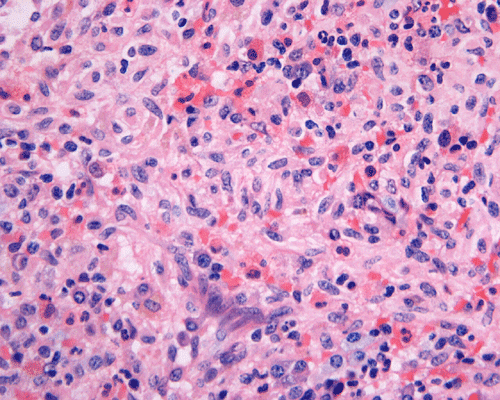

Clinical information The patient was a 73 year-old man with an itchy skin rash, hepatosplenomegaly, and gastrointestinal bleeding.  On admission, his complete blood count (CBC) showed an elevated white count (21,000/cm3) with 25% monocytes and 16% eosinophils, hemoglobin of 9.8 g/dL and 8,000 platelets/cm3.  His 24-hour urine histamine was >200 mg/mL (ref 5.6-13.5 mg/mL). A bone marrow biopsy was performed and the representative photomicrographs are illustrated below:

Normal mast cells have a round or oval, centrally located nucleus with uniform distribution of dark purple granules in the cytoplasm.  Mast cells are well demonstrated by toludine blue and Giemsa stains, and also by immunohistochemistry for CD 117 or tryptase. Napthol ASD chloracetate esterase also highlight mast cells specifically. Mast cells are also positive for CD45, CD33, and CD68 but these markers are less specific than tryptase.  Bone marrow aspirations stained with Giemsa are most useful for recognizing atypia in mast cells. It should, however, note that Giemsa stain may be false negative in formalin fided tissue. Hallmarks of atypia in mast cells include spindling of mast cells, hypogranulation, uneven granule distribution, and nuclear lobulation.  Recognition of the so-called mast cell granuloma, in which mast cell aggregrates are associated with lymphocytes and eosinophils can be helpful.

In the bone marrow, three morphologic patterns of mast cell accumulation have been recognized.  Type I shows focal clusters of mast cells with preservation of bone marrow fat and other hematopoetic elements.  The burden of mast cells is more in Type II and usually shows patchy clusters of mast cell replacing bone marrow in a hypercellular marrow background with osteosclerosis and fibrosis.  Type III is diffuse replacement of the marrow space with mast cells, often with circulating mast cells in peripheral blood.  It is also important to note that mast cells are easily over looked on routine H and E stain or are mistaken for histiocytes.

By flow cytometry, aberrant expression of CD 25 and CD 2 has been used to define an atypical population of mast cells.  About 95% of systemic mast cell disease cases aberrantly express CD 25 and 70% aberrantly express CD 2.